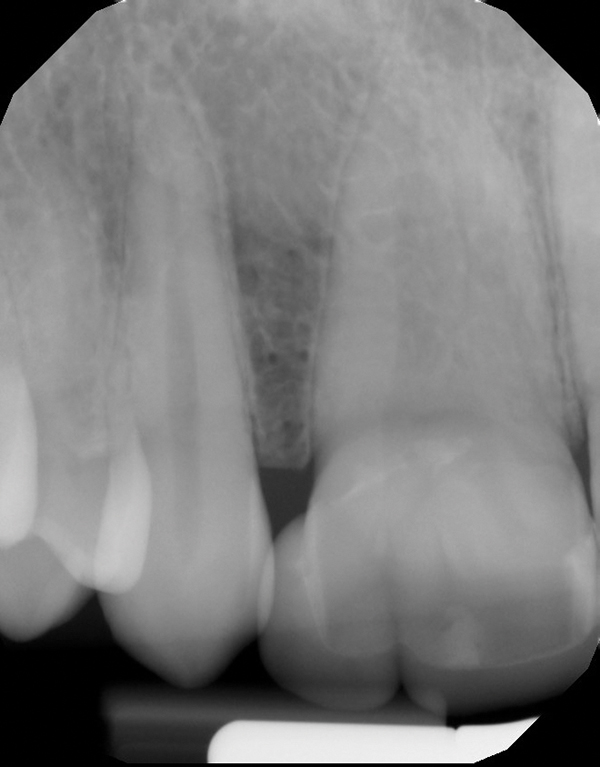

Fig 1 and Fig 2. Pretreatment photographs. Patient at 9 years of age on presentation.

A 9-year-old girl, referred to a prosthodontic office by her pediatric dentist, presented with her mother’s chief complaint: “The kids are teasing her about her big front tooth.” Findings from radiographic and clinical examinations revealed fused maxillary central-peg lateral incisors, teeth Nos. 7 and 8, and a congenitally missing lateral incisor, tooth No. 10 (Figure 1 through Figure 3). An implant was selected as the ideal treatment to replace tooth No. 10 when somatic growth was complete. A diagnostic wax-up was fabricated to determine if the fused tooth could be made to resemble two teeth, using pink composite to give the illusion of an interproximal papilla. The patient was referred for an orthodontic consultation to plan for closure of the diastema between teeth Nos. 8 and 9 and achievement of proper alignment for implant No. 10. The patient was also referred to a periodontist for pretreatment assessment of the tooth No. 10 site. An endodontist was consulted should exposure of the large pulp occur during tooth preparation.